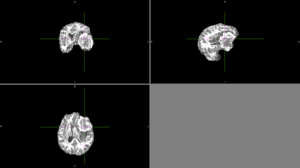

Semi-automatic segmentation with Slicer was relatively successful. Sometimes the segmentation would bleed outside of the tumor into voxels with similar intensities.

We tried FSL's FAST with different numbers of classes. None of these methods could identify the entire tumor mass as one type of tissue in this scan.